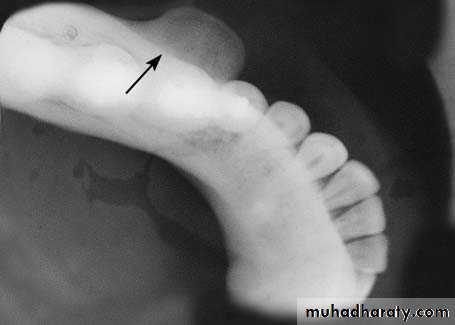

Clinically, it is an asymptomatic bony protuberance covered by normal mucosa. Radiographically, it presents as a circumscribed radiopacity in the area of localization.